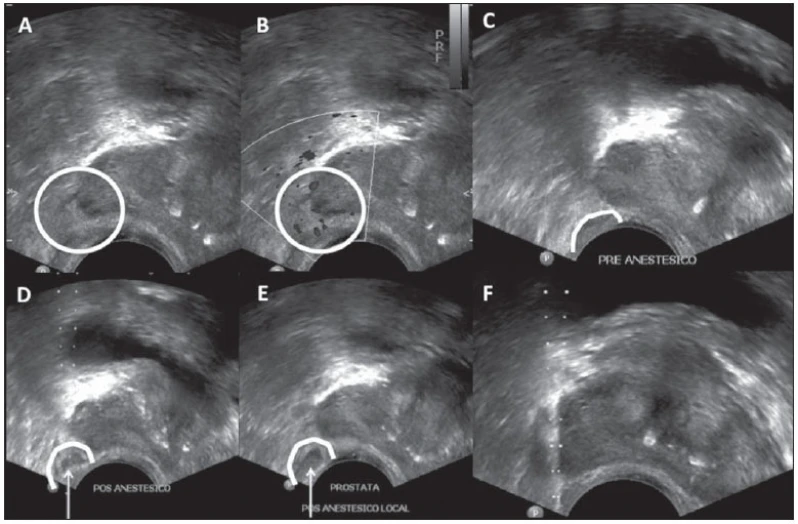

Procurou por penioscopia com biopsia em Sapopemba? Encontre a solução que você precisa aqui na DK Urologistas. São diversas opções disponibilizadas, como urologistas, biopsia de próstata, vasectomia, cirurgias de fimose, disfunção erétil, ejaculação precoce e estudo urodinâmico. Para tal sucesso, a empresa investiu em profissionais competentes e em equipamentos inovadores.